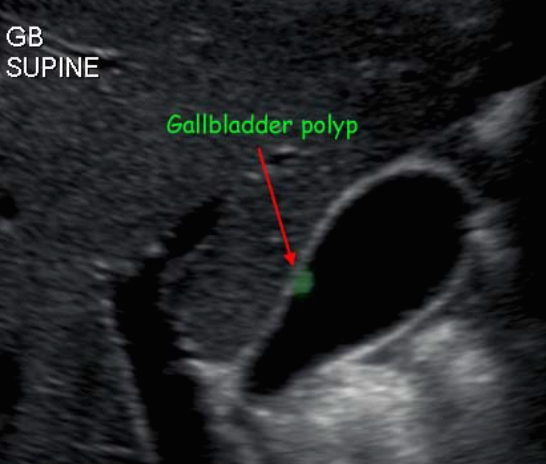

담낭 용종 ( GB polyp ) 담낭 안쪽 벽에서 담낭 안으로 돌출된 다양한 형태의 점막이 두꺼워진 것이다. 용종 자체로는 큰 문제를 일으키지 않으나, 용종의 크기가 커지면 암으로 변할 가능성이 높다. 용종의 크기가 직경 10mm 이상인경우 악성일 가능성이 높다.

발생빈도는 성인의 약 3~7% 정도이고 남성보다는 여성에서 2배 정도로 많으며 40대에서 많이 발생한다. 증상이 없으며 우연히 발견되나 드물게 명치끝이나 우상복부에 통증을 호소하는 경우도 있다.

1cm 이상의 담낭 용종은 수술로 담낭 전체를 제거하는 것을 원칙으로 하고, 1cm 미만인 경우는 주기적인 추적관찰을 한다. 용종의 크기가 1cm 미만이라 하더라도 담석이 동반되어 있거나, 증상( 복통, 담낭염등)이 있는 경우는 제거하는 것이 좋다.

1. 콜레스테롤 용종 (cholesterol polyp) : 50~90%로 가장 흔한 타입

- 1cm 미만의 고에코의 종괴 (hyperechoic mass) : 담석에 비해 에코가 낮고, 담낭벽보다는 고에코로 보임

- 담낭벽에 붙어 체위변화 시 이동이 없다

- 후방음영이 없다